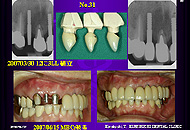

しかし、既にAQBを植立しCrが入り、第二の永久歯を実感した患者さんが、さらに他部位の植立を希望している場合、直径4mmを植立予定で手術時フラップを開けてみたが、直径4mmはとても無理であるという顎骨に遭遇することがある。

患者さんの強い願望に負け、上部構造を連結すれば何とかなるかなという思いで、2003年から恐る恐る植立して、経過をみはじめた。

下顎前歯部以外に植立した直径3mm症例はIAI 研究会第9回学術大会で発表した2006年8月までの3年間で、20症例47本であった。

発表に際して直径3mm症例の安全な植立と補綴法をしっかり考察したこともあり、その後この1年間で、さらに21症例50本が追加され、2003年から下顎前歯部以外に植立した直径3mmAQBは計41症例97本となっている。いくら下顎前歯部は欠損しにくい部位であるといっても、同じ時期に下顎前歯部に植立した3mmAQBが5症例7本であるから、私は直径3mmAQBを下顎前歯部以外に植立し始めてから、適応症が大きく拡大したことになる。